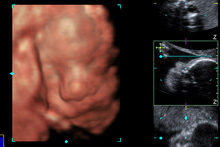

Essa manhã fizemos uma ultrasonografia 3d-4d, foi ótimo ver a Julia novamente e como ela cresceu desde a ultrasom que fizemos com 19 semanas (estou com 27 semanas). Fomos na Siemens, que oferece essas ultras de graça para testar o software de ultrassom deles. Eu realmente não queria gastar $200 para fazer uma ultra 3d-4d porque simplesmente acho a qualidade das imagens uma porcaria, gosto muito mais da ultrasonografia 2d tradicional do que da 3d-4d. Não consigo achar legal, o bebê parece todo deformado, muito bizarro. Mas como era de graça…hehe. Eles nos deram um CD com algumas poucas fotos e uns videozinhos, então vou colocar aqui para vocês verem, mesmo eu achando as imagens estranhíssimas.

Momentos legais: ela estava com a mãozinha na frente do rosto a maior parte do tempo e mexendo a boquinha. Ela estava de perninhas cruzadas! Descobri que o ovo na minha barriga do lado direito que sinto quase o tempo todo é o bumbum dela e os pés estão à esquerda do meu umbigo. E a técnica de ultrassom confirmou que é uma menina mesmo, sem dúvidas. Esqueci de falar antes: vimos o cabelo dela! O cabelinho está compridinho, por isso que deu pra ver, atrás da cabeça, logo acima da nuca.

que linda!!! a que eu gostei mais foi a foto escura que ela está de perfil!! que narizinho mais lindo!!!!

Nao se engane, a ultra 3D mostra sim as feicoes reais do bebe. Claro que qdo nascem ja estao maiores ate, mas eh aquilo mesmo.

Ai que gostoso! Ela é uma fofa e que narizinho mais arribitadinho, digno de uma princesinha. Parabéns! Bjs!

Muito legal a ultra 3d. Essa imagem da Julia de perfil é muito importante. Quando eu fiz, o médico mediu o comprimento do narizinho do Pedro e disse que a medida do nariz (que só é possível com esta imagem), é um dos parâmetros utilizados para determinar se o bebê tem Síndrome de Down, pois estes bebês geralmente tem o nariz bem curtinho, que não é o caso da Julia.